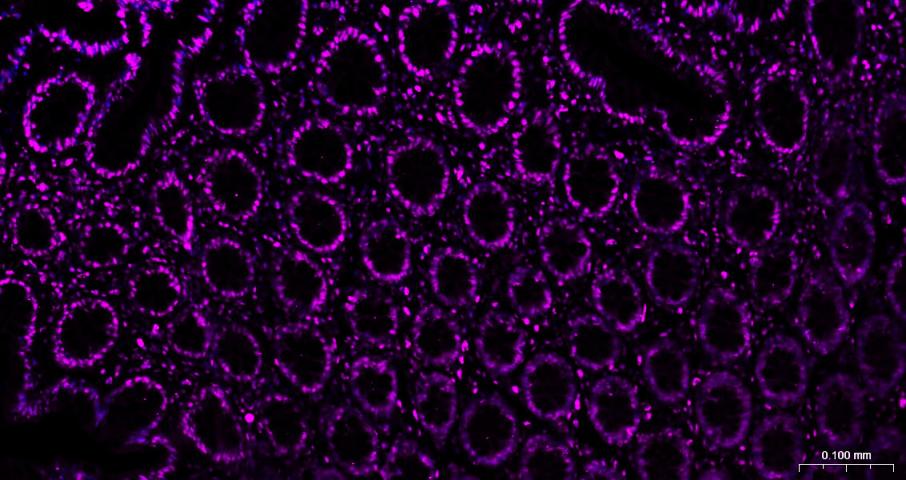

Paraformaldehyde-fixed, paraffin embedded Human Colon; Antigen retrieval by boiling in sodium citrate buffer (pH6.0) for 15 min; Antibody incubation with Histone H3 Monoclonal Antibody, Unconjugated (bsm-33042M) at 1:200 overnight at 4°C. Followed by conjugated Goat Anti-Mouse IgG antibody (Purple, bs-0296G-Cy5), DAPI (blue, C02-04002) was used to stain the cell nuclei.